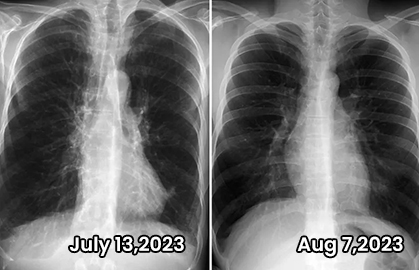

Witness the Truly Life-changing Results of 10,000+ Sheenice Users

After years of on and off smoking and vaping I decided to quit! So I got this to help clear out some of the gunk in my lungs! Has it helped?YES! After using Sheenice for just one month, I went to the hospital for a checkup, and the doctor told me that my emphysema had disappeared.  It can be really difficult to find good quality organic products like this one that are affordable! Highly recommend!

--David Jonas